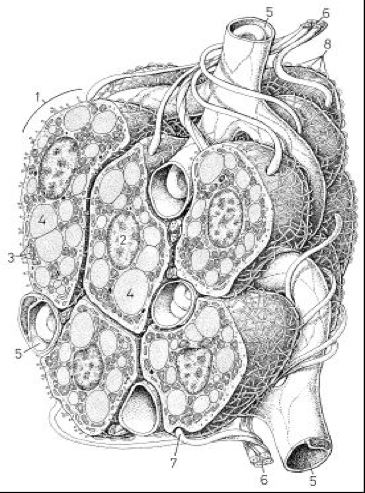

TA BLANC1 - Noyau

2 - Mitochondries

3 - Cytoplasme

4 - Enclave lipidique

5 - Densification du réseau microfibrillaire cytoplasmique

6 - Trame ayant valeur de membrane basale

7 - Membrane plasmique

8 - Fibres de réticuline

TA BRUN1 - Cellule (adipocyte)

2 - Noyau (central)

3 - Réticulum Endoplasmique

4 - Enclaves lipidiques

5 - Vaisseaux sanguins

6 - Fibres nerveuses

7 - Terminaisons nerveuses sur les cellules

La densification du réseau cytoplasmique et la membrane sont pas représentés sur ce schéma mais sont bien présents